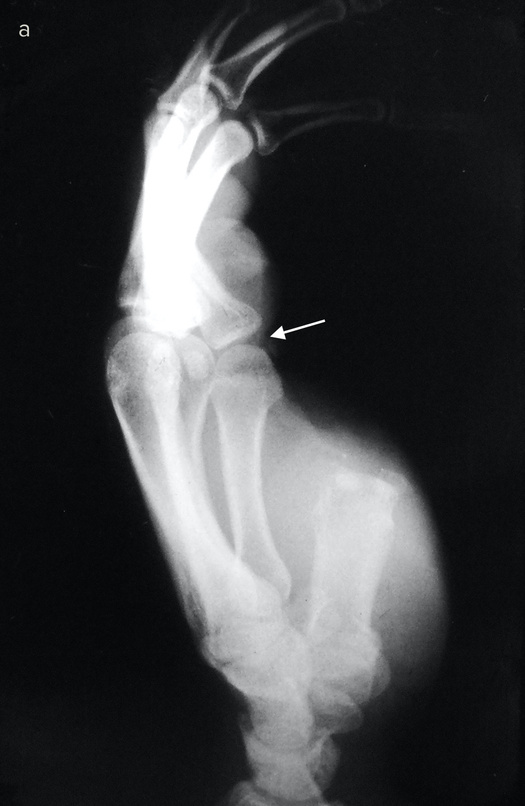

Если восстановить или приживить эту важнейшую часть кисти невозможно, ее реконструируют. Существует три основные методики, которые я условно называю «упросить», «одолжить» и «украсть». В первом случае хирург и пациент как бы упрашивают обрубок большого пальца вырасти в длину. С обоих концов оставшейся кости хирург вставляет поперечные стальные шпильки, прикрепляет эти шпильки к стальной раме и разрезает кость между ними.

Пациент каждый час поворачивает небольшую ручку этого приспособления, напоминающего аппарат Илизарова, и по чуть-чуть увеличивает промежуток между фрагментами кости. Процедура длится от шести до восьми недель. Кость и окружающие ее мышцы, сухожилия, нервы и кожа едва ли понимают, что их растягивают: для них это просто какой-то очень быстрый рост, и им надо успеть.

Когда большой палец вновь обретает рабочую длину, хирург заполняет промежуток костным трансплантатом. Преимущество такого способа удлинения в том, что не приходится ничего «одалживать» или «красть». Однако не все так радужно: ноготь и отсутствующие суставы большого пальца уже не вернуть.